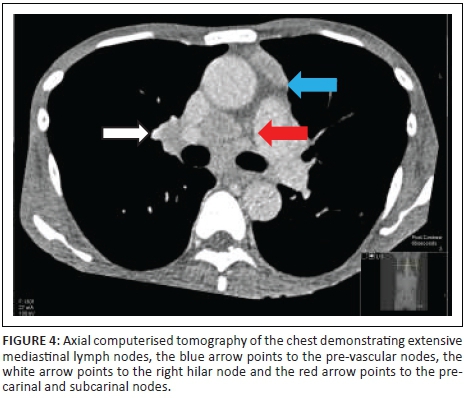

A chest radiograph demonstrated right basal opacification. Computerised tomography of the chest abdomen and pelvis (CT-CAP) revealed patchy air space opacification at the left oblique fissure, left lower and right lower lobes, paraseptal and central lobular emphysema and bibasal atelectasis (Figures 1 and 2). Hepatosplenomegaly was confirmed and free fluid was evident throughout the abdomen and pelvis (Figure 3). Multiple enlarged lymph nodes (up to 1.8 cm diameter) were visualised throughout the thorax, abdomen and pelvis (Figures 4 and 5).

The patient presented our multi-disciplinary team with a diagnostic challenge. Given his clinical presentation including low CD4 count, mycobacterial infection was felt to be the most likely diagnosis. However, radiological imaging highlighted significant, widespread lymphadenopathy throughout the thorax, abdomen and pelvis, which was later confirmed by tissue diagnosis to be HL.

Widespread homogenous lymphadenopathy may be a feature of both MAC and HL; however, lymphadenopathy is often massive in HL (> 3 cm diameter).5 Hepatosplenomegaly is commoner in MAC than in HL.5 HL tends to be seen with a CD4 count around 240 cells/μL4; in contrast, disseminated MAC is typically found with CD4 < 50 cells/μL.1